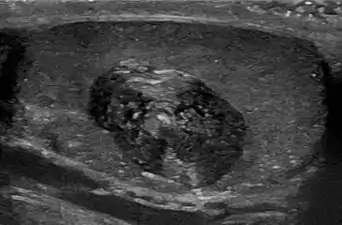

- Epidermoid cyst in a testicle on ultrasound, with lamellated ("onion skin") appearance